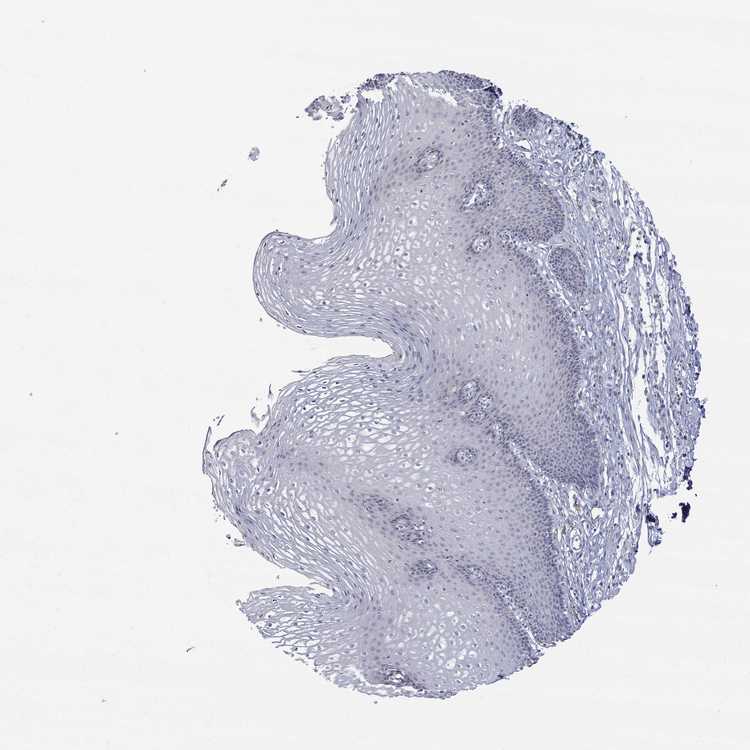

TISSUE PRIMARY DATA ESOPHAGUS Show tissue menu

ESOPHAGUS - Antibody stainingi

Antibody staining in the annotated cell types in the current human tissue is reported as not detected, low, medium, or high, based on conventional immunohistochemistry profiling in selected tissues. This score is based on the combination of the staining intensity and fraction of stained cells.

Each image is clickable and will lead to virtual microscopy that enables deeper exploration of all samples and also displays staining intensity scores, fraction scores and subcellular localization as well as patient and tissue information for each sample.

Antibody HPA051290

Squamous epithelial cells Not detected